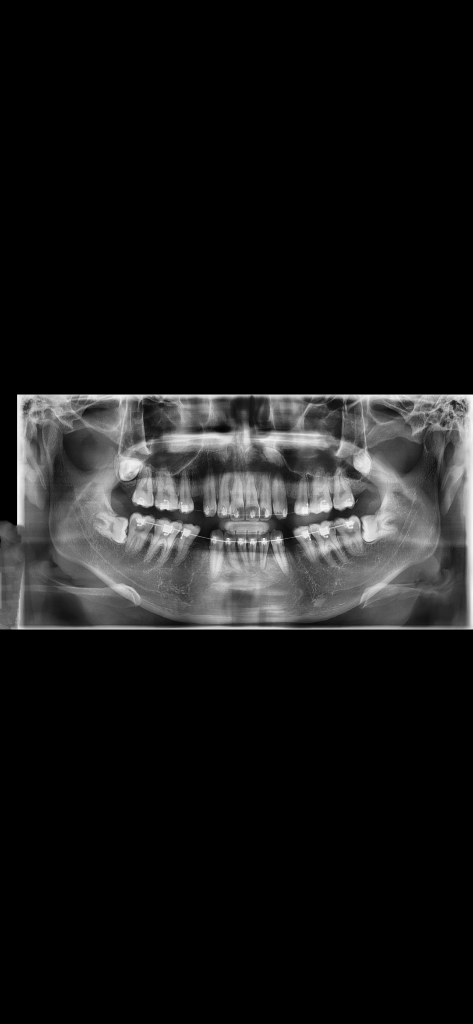

파노라마 사진인데 사랑니 이정도면

위에는 뺄 필요 없다고 들어씨고 밑에 두개는 빼야된다고 하는데 두개 다 의사님들이 보실때 빼는 난이도가 어떻게 되나요?? 어금니 뒤쪽에 육안으로도 살짝 보여요

사진상으로는 사랑니 중 중간 정도의 난이도로 보입니다. 너무 걱정하실 필요는 없어보입니다.

아래 사랑니 2개 다 옆으로 누워있는 수평매복 사랑니 입니다. 수술적 방법으로 치아를 절단하고 잇몸뼈 일부 삭제하고 뽑아야 하니 난이도가 높은 편입니다.

기울어져 있는 사랑니는 발치 난이도가 높은 편에 속합니다.

난이도가 쉽지는 않아 보입니다. 사랑니가 꽤 깊숙히 잇고 완전이 수평매복이기 떄문에 일반치과에서는 발치를 못할수도 있습니다.

난이도의 경우 거의 완전매복에 가까운 부분매복 사랑니인데 다행이도 앞의 두번째 큰 어금니과 겹치는 부분이 없으므로 아주 어렵지는 않을 것 같습니다.

잇몸을 절개하고 뼈를 조금 제거한 뒤 사랑니 머리부터 분할해서 뽑을 것 같습니다.